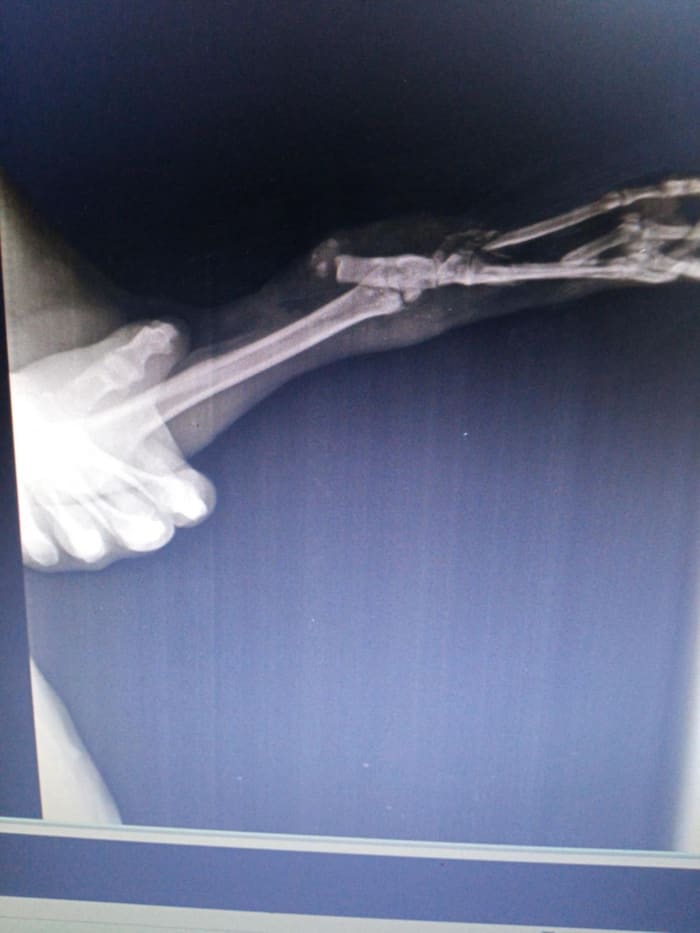

Pauna was rescued by Akrity in her area with a badly damaged right rear leg. The leg was so damaged it had to be amputated as a repair was not possible. He did not have a place to go back to, so he is staying in our rescue centre. He needs a sponsor.